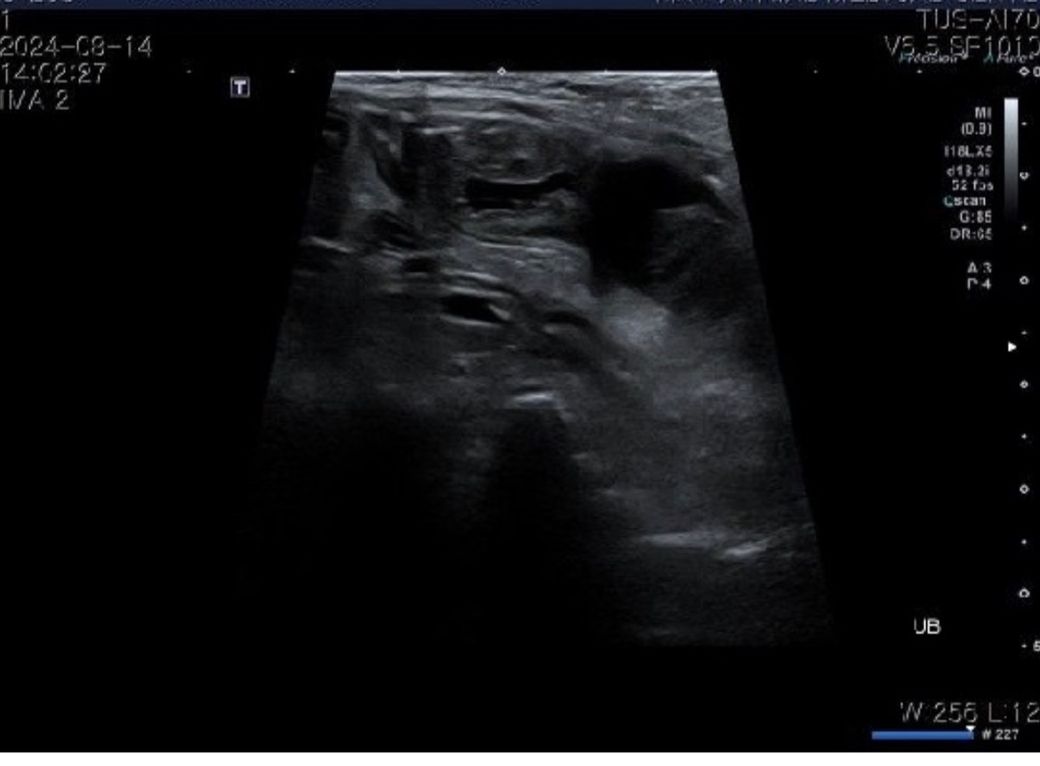

방광 종양 초음파 전,후 설명 부탁드리겠습니다ㅠ

후(조직검사 떼고나서 찍은거 같습니다?)

초음파 검사는 다른 영상검사와 다르게 정지화상으로 얻을 수 있는 데이터는 적고, 임상적 의미도 거의 없습니다.

검사를 하는 과정에서의 동시성이 무엇보다 중요합니다. 즉, 검사를 한 초음파 검사자의 소견이 가장 중요한요소로 정지화상만으로 평가하는것은 오만에 가까운 위험한 행동입니다.